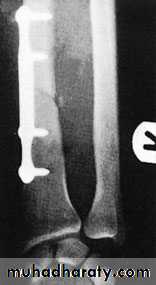

The key to successful treatment is to restore the length of the fractured ulna; only then can the dislocated joint be fully reduced and remain stable. In adults, this means an operation through a posterior approach. The ulnar fracture must be accurately reduced, with the bone restored to full length, and then fixed with a plate and screws.but in children closed reduction and plaster is usually satisfactoryChildren Rx Adult Rx

A transverse or short oblique fracture is seen in the lower third of the radius, with angulation or overlap. The distal radio-ulnar joint is subluxated or dislocated.Treatment

As with the Monteggia fracture, the important step is to restore the length of the fractured bone. In children, closed reduction is often successful; in adults, reduction is best achieved by open operation and compression plating of the radius.